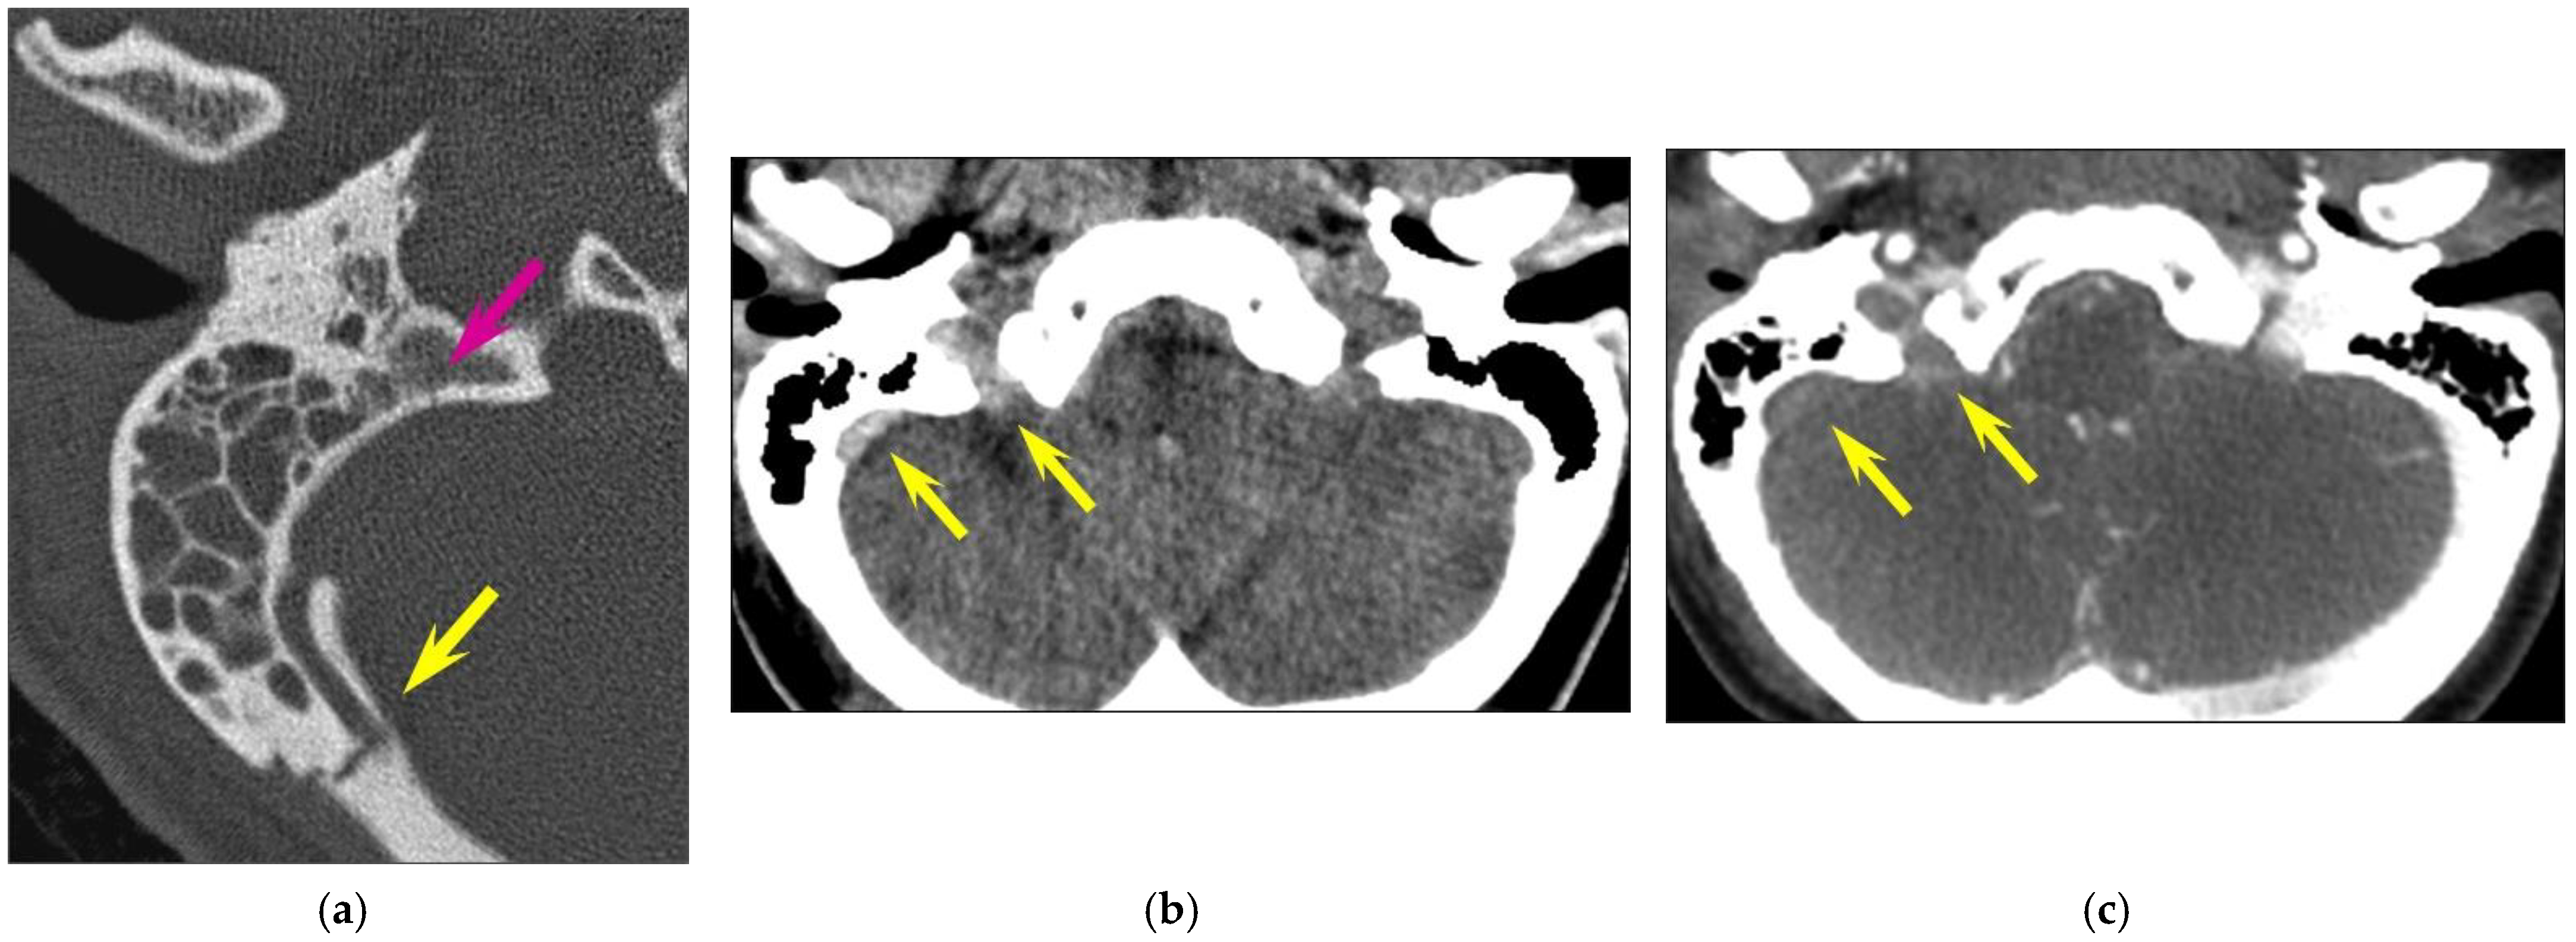

Figure 4. Vascular injuries. Longitudinal fracture of the right temporal bone and venous thrombosis in a 30-year-old woman involved in a motorway traffic accident. CT of the posterior fossa (a,b) unenhanced CT; (c): intravenous contrast-enhanced CT. (a) A detached fragment of the posterior part of the temporal bone, projecting into the sigmoid sinus (yellow arrow); the fracture line is also seen more medially (pink arrow). (b): spontaneous hyperdensity of the sigmoid sinus and of the jugular foramen (yellow arrows). (c) The absence of the opacification of these vascular structures, consistent with venous thrombosis (yellow arrows).

In 22 fractures (22/126, 17.5%), the fracture line involved the carotid canal, but only one case (1/126, 0.8% of all temporal bone fractures; 1/22, 4.5% of fractures involving the carotid canal) showed associated focal internal carotid artery dissection. In 23 cases (23/126, 18.3%), the fracture line extended to the sigmoid groove of the petrous temporal bone; thrombosis of the sigmoid sinus (Figure 4) was present in 4 cases (4/126, 3.2% of all temporal bone fractures; 4/23, 17.4% of fractures involving the sigmoid groove).

A study found that 3.4% of head injuries were associated with petrous temporal bone fractures [22]. The reported incidence of dural venous thrombosis in association with temporal bone fracture, more so with those crossing the dural sinus or jugular bulb, is about 40.7% [25]. When the fracture involves the petrous portion of the temporal bone, the reported incidence of dural venous thrombosis is 22.4% [26]. In our study, the incidence of dural venous thrombosis was 17.4% in fractures involving the sigmoid groove of the petrous temporal bone. It is worth mentioning that no venous thrombosis was detected via CT whenever the fracture line did not involve the sigmoid groove. We had also one internal carotid dissection in an adult (0.8% of all temporal bone fractures and 4.5% of fractures involving the carotid canal). Internal carotid artery injury is reported to occur in 1% of all adult patients with severe head trauma [27] and in up to 9.4% of patients with petrous temporal bone fractures [28]. Complications include hemorrhage, pseudoaneurysm formation, carotid cavernous fistula, stroke and death, with a reported in-hospital mortality rate of up to 45.5% [28]. According to some authors, in adult patients with petrous temporal bone fractures, factors clearly associated with internal carotid artery injury include carotid canal fractures and motor vehicle or motorbike crashes as trauma mechanisms [28]. As these patients have an increased risk of internal carotid injury, some authors have recommended routine screening for internal carotid artery injury using CT angiography [28]. Internal carotid artery injury is only rarely seen in the pediatric population, and data are limited to isolated case reports. Nevertheless, for cranial trauma in children, fractures of the petrous temporal bone or through the carotid canal have been shown to be independent factors for blunt cerebrovascular injury [29].